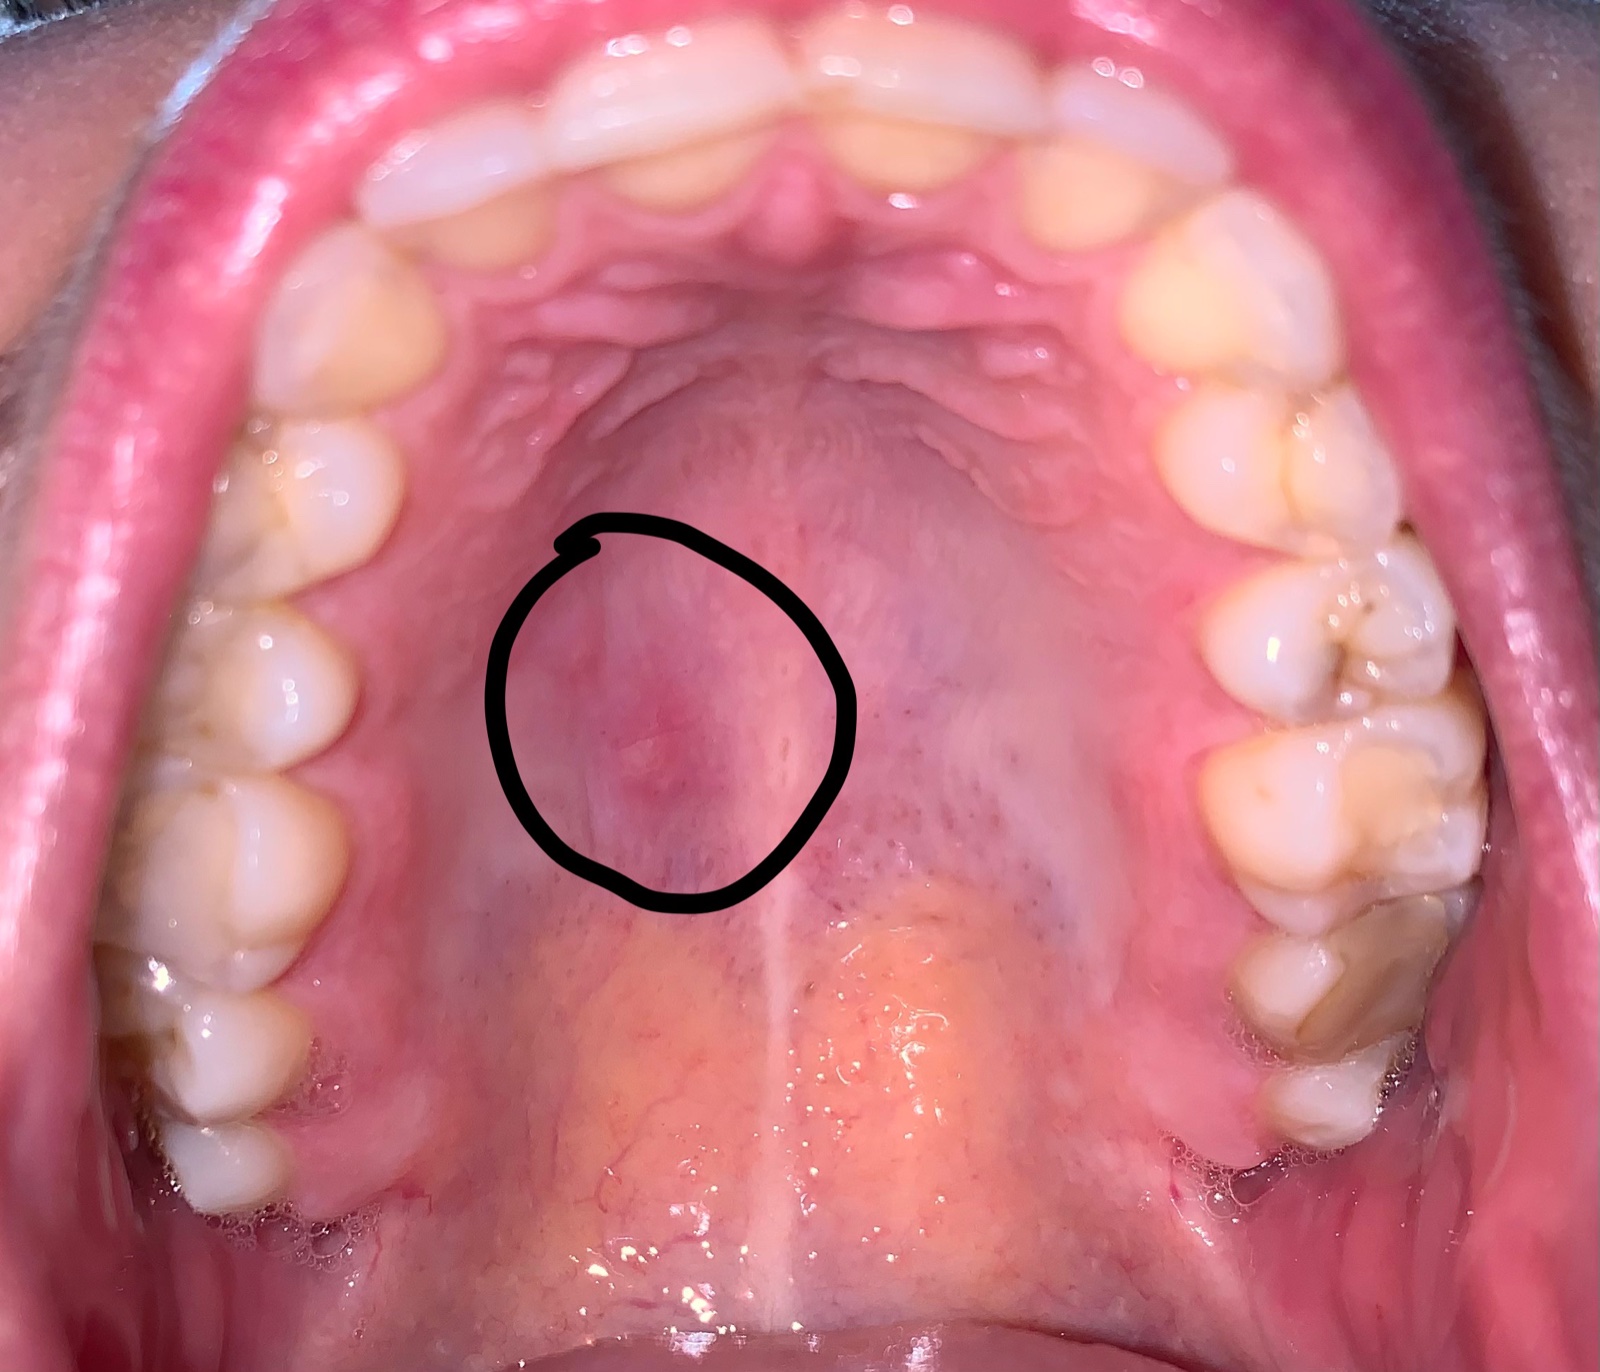

chcela by som sa poradiť ohľadom môjho problému. Na podnebí mám dlhodobo tvrdú gulôčku.

O aký problém ide?

môže ísť o drobnú cystu. Okolie je začervenané, preto by bolo vhodné si aspoň tri dni vyplachovať ústnu dutinu roztokmi - ako napr. Tantum verde alebo Garganta.

Ak by ste chceli presne vedieť o čo ide, tak je vhodné doplniť ORL vyšetrenie.